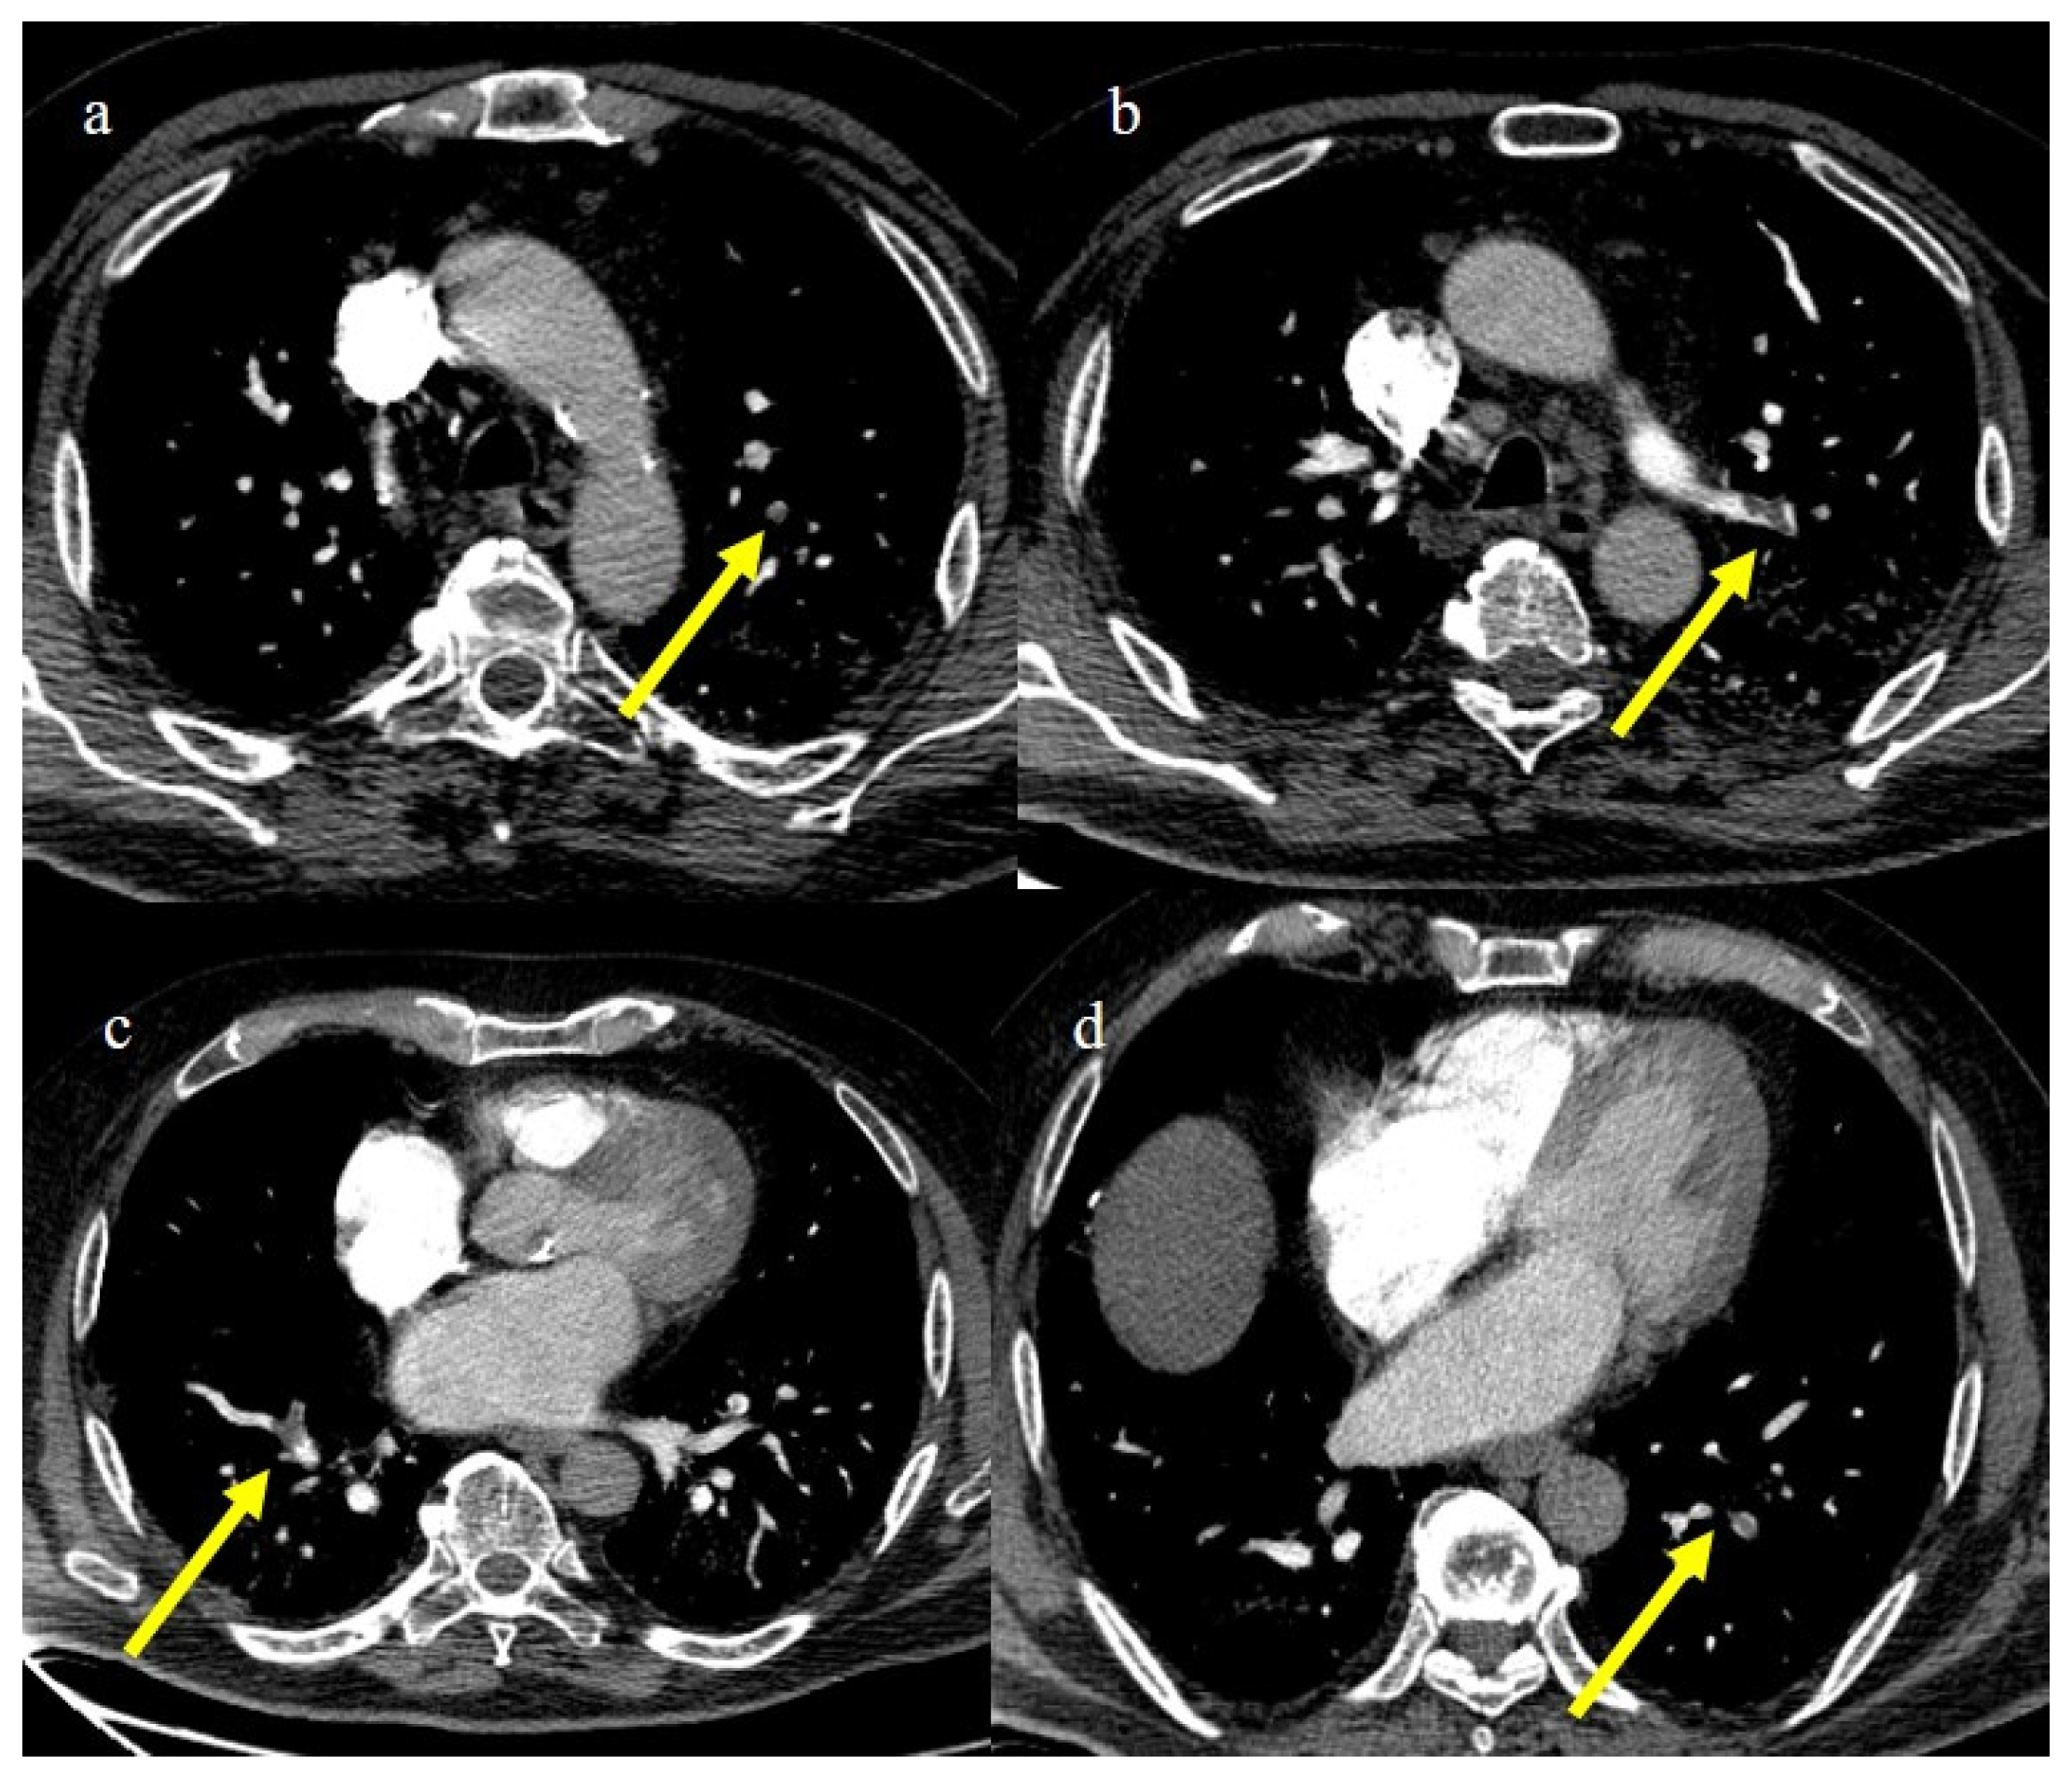

- Castro, G.R.A.; Collaço, I.A.; Bosco, C.L.B.D.; Corrêa, G.G.; Bosco, G.B.D.; Corrêa, G.L. Splenic infarction as a complication of covid-19 in a patient without respiratory symptoms: A case report and literature review. IDCases 2021, 24, e01062. [Google Scholar] [CrossRef] [PubMed]

- Prentice, G.; Wilson, S.; Coupland, A.; Bicknell, S. Complete splenic infarction in association with COVID-19. BMJ Case Rep. 2021, 14, e246274. [Google Scholar] [CrossRef] [PubMed]

- Al Suwaidi, S.; Alakasheh, B.J.; Al-Ozaibi, L.S. Splenic Infarction in a COVID-19 Patient without Respiratory Symptoms. Dubai Med. J. 2022, 5, 74–77. [Google Scholar] [CrossRef]

- Childers, J.; Do, T.V.C.; Smith, F.; Vangara, A.; Ganti, S.S.; Akella, R. Incidental and Asymptomatic Splenic Infarction and Infrarenal Thrombus in a COVID-19 Patient. Cureus 2022, 14, e26555. [Google Scholar] [CrossRef] [PubMed]

- Post, A.; den Deurwaarder, E.S.G.; Bakker, S.J.L.; de Haas, R.J.; van Meurs, M.; Gansevoort, R.T.; Berger, S.P. Kidney Infarction in Patients with COVID-19. Am. J. Kidney Dis. 2020, 76, 431–435. [Google Scholar] [CrossRef]

- Jana, K.; Janga, K.C.; Greenberg, S.; Kumar, K. Bilateral renal infarction with COVID-19 pneumonia: A case report. Oxf. Med. Case Rep. 2021, 2021, omab121. [Google Scholar] [CrossRef]

- Murray, N.P.; Fuentealba, C.; Reyes, E.; Salazar, A. Renal infarction associated with asymptomatic COVID-19 infection. Hematol. Transfus. Cell Ther. 2021, 43, 353–356. [Google Scholar] [CrossRef]

- Plouffe, B.; Van Hooren, T.; Barton, M.; Nashid, N.; Demirkaya, E.; Norozi, K.; Rachinsky, I.; Delport, J.; Knauer, M.; Tole, S.; et al. Renal Infarcts—A Perplexing Case in the Middle of the COVID-19 Pandemic. Front. Pediatr. 2021, 9, 669453. [Google Scholar] [CrossRef]

- Gentili, G.; Pérez, P.L.; Laplumé-Elizalde, E.; España, S. Kidney infarction in patient with covid-19: Clinical case. Am. J. Kidney Dis. 2022, 82, 788. [Google Scholar] [CrossRef]

- Al-Mashdali, A.F.; Alwarqi, A.F.; Elawad, S.M. Simultaneous renal infarction and splenic infarction as a possible initial manifestation of COVID-19: A case report. Clin. Case Rep. 2021, 9, 4819. [Google Scholar] [CrossRef]

- Brem, F.L.; Abu Al Tayef, T.; Rasras, H.; El Mahi, O.; El Ouafi, N.; Zakaria, B. Concomitant renal and splenic infarctions in a COVID-19-patient with a catastrophic thrombotic syndrome. Radiol. Case Rep. 2022, 17, 4030–4033. [Google Scholar] [CrossRef]

- Ramanathan, M.; Chueng, T.; Fernandez, E.; Gonzales-Zamora, J. Concomitant renal and splenic infarction as a complication of COVID-19: A case report and literature review. Infez. Med. 2020, 28, 611–615. [Google Scholar]

- Mavraganis, G.; Ioannou, S.; Kallianos, A.; Rentziou, G.; Trakada, G. A COVID-19 Patient with Simultaneous Renal Infarct, Splenic Infarct and Aortic Thrombosis during the Severe Disease. Healthcare 2022, 10, 150. [Google Scholar] [CrossRef]

- Dimitriou, I.; Christodoulou, N.; Chatzimargaritis, K.; Kaikis, A.; Kasti, E.; Triantos, G. Splenic Artery Infarct Requiring Surgery: A Rare Complication of COVID-19 Infection. Case Rep. Surg. 2022, 2022, e3391405. [Google Scholar] [CrossRef]

- Javaid, U.; Young, P.; Gill, G.; Bhargava, P. Acute complete splenic infarction secondary to COVID-19 infection. Radiol. Case Rep. 2022, 17, 1402–1406. [Google Scholar] [CrossRef]